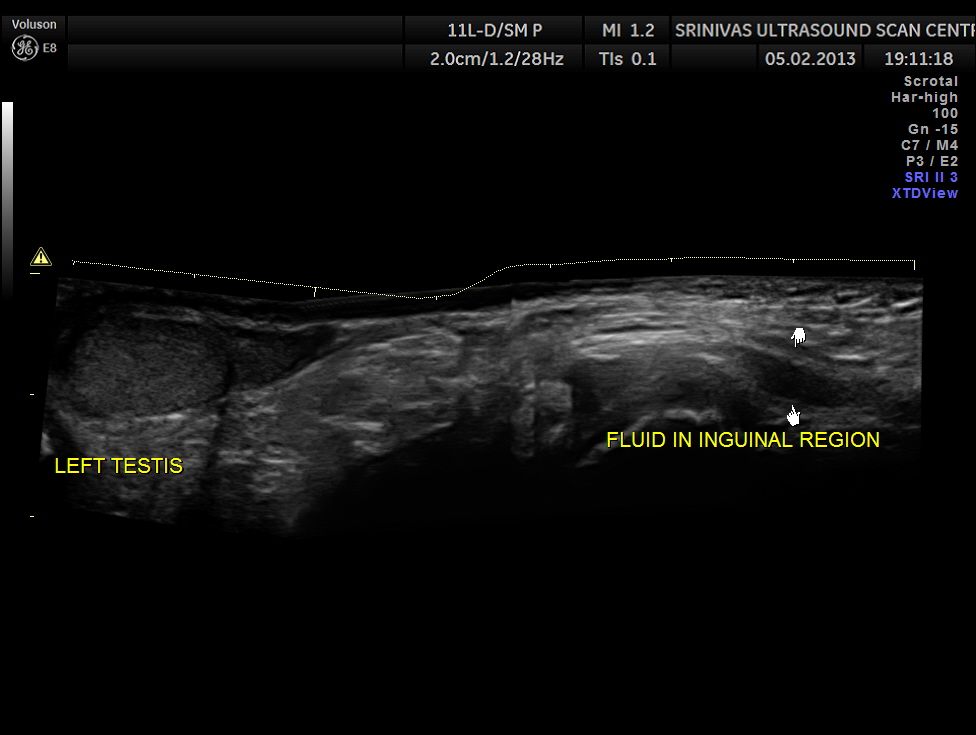

This was a 11 year old boy referred for evaluation of left inguinal swelling on and off.

The clinical diagnosis was bubunocele.

(medicine) An inguinal hernia, especially of the incomplete variety in which the hernial pouch descends only as far as the groin, forming a swelling there like a bubo.

An inguinal hernia, especially one in which the knuckle of intestine has not yet emerged from the external abdominal ring.